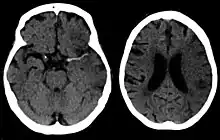

| CT scan of the brain showing a prior right-sided ischemic stroke from blockage of an artery. Changes on a CT may not be visible early on.[1] | |

The biggest risk factor for stroke is high blood pressure.[7] Other risk factors include high blood cholesterol, tobacco smoking, obesity, diabetes mellitus, a previous TIA, end-stage kidney disease, and atrial fibrillation.[2][7][8] Ischemic stroke is typically caused by blockage of a blood vessel, though there are also less common causes.[13][14][15] Hemorrhagic stroke is caused by either bleeding directly into the brain or into the space between the brain's membranes.[13][16] Bleeding may occur due to a ruptured brain aneurysm.[13] Diagnosis is typically based on a physical exam and supported by medical imaging such as a CT scan or MRI scan.[9] A CT scan can rule out bleeding, but may not necessarily rule out ischemia, which early on typically does not show up on a CT scan.[10] Other tests such as an electrocardiogram (ECG) and blood tests are done to determine risk factors and rule out other possible causes.[9] Low blood sugar may cause similar symptoms.[9]

For diagnosing ischemic (blockage) stroke in the emergency setting:[69]

- CT scans (without contrast enhancements)

- sensitivity= 16% (less than 10% within first 3 hours of symptom onset)

- specificity= 96%

- MRI scan

- sensitivity= 83%

- specificity= 98%

For diagnosing hemorrhagic stroke in the emergency setting:

- sensitivity= 89%

- specificity= 100%

- sensitivity= 81%

For detecting chronic hemorrhages, an MRI scan is more sensitive.[70]

CT scans may not detect ischemic stroke, especially if it is small, of recent onset,[10] or in the brainstem or cerebellum areas (posterior circulation infarct). MRI is better at detecting a posterior circulation infarct with diffusion-weighted imaging.[71] A CT scan is used more to rule out certain stroke mimics and detect bleeding.[10] The presence of leptomeningeal collateral circulation in the brain is associated with better clinical outcomes after recanalization treatment.[72] Cerebrovascular reserve capacity is another factor that affects stroke outcome – it is the amount of increase in cerebral blood flow after a purposeful stimulation of blood flow by the physician, such as by giving inhaled carbon dioxide or intravenous acetazolamide. The increase in blood flow can be measured by PET scan or transcranial doppler sonography.[73] However, in people with obstruction of the internal carotid artery of one side, the presence of leptomeningeal collateral circulation is associated with reduced cerebral reserve capacity.[74]